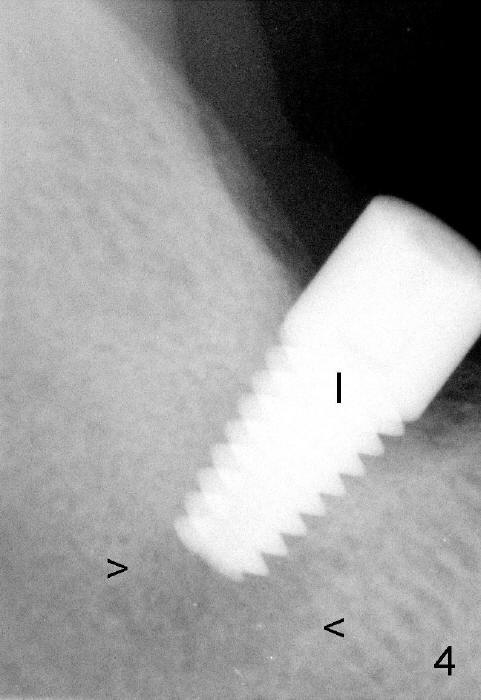

It is advantageous to place implant immediately or shortly (4-8 weeks) after extraction.  But most teeth to be extracted are potentially infected, such as in the case of Ms. Pei (Fig.1).  Periapical radiolucency (PARL) is not obvious prior to extraction. Six weeks post-extraction, osteotomy is finished with bone expansion and drilling (Fig.2 D, 5x14mm).  Tatum tapered implant is placed (Fig.3 I: 6x14). So far PARL is minimal if any (Fig.2,3 <).  Pain develops approximately 20 days post-implantation with expanding PARL (Fig.4 <).  Antibiotic treatment does not resolve the infection.  The implant has to be removed.  Infected granulation tissue is thoroughly removed from the apical portion of  the socket (Fig.5 <) with a curette (C).  Scaling and root planing is done for 4 quadrants.  A month later, potentially infected hard tissue is removed by reamers (Fig.6 D, 5 mm).  Bicon implant is buried inside the bone and separated from the oral cavity (Fig.7 I, 5x8).  At that time, there is a gap next to the implant (>).  Five months later, the gap disappears, suggesting implant osteointegration (Fig.8).  Extraoral cementation is done between abutment (A) and crown (C).  The abutment/crown unit is tapped into the implant with 2 visible threads (<).  The latter indicates that the abutment is completely seated.  Dashed lines in Fig.5-7 denote the upper border of the inferior alveolar canal.  PAs are taken 6 months (Fig.9) and 1 year 7 months (Fig.10) post cementation.  In all, it is a hassle to do re-implantation.  Efforts should be exerted to prevent post-implant infection.

1. Prior to implantation, ask the patient whether he/she has taken an antibiotic if there is possible infection, e.g., root canal failure (Fig.1 <: separated file, no crown). If not, give the patient 2 gm of Amoxicillin or 600 mg Clindamycin if there is penicillin allergy